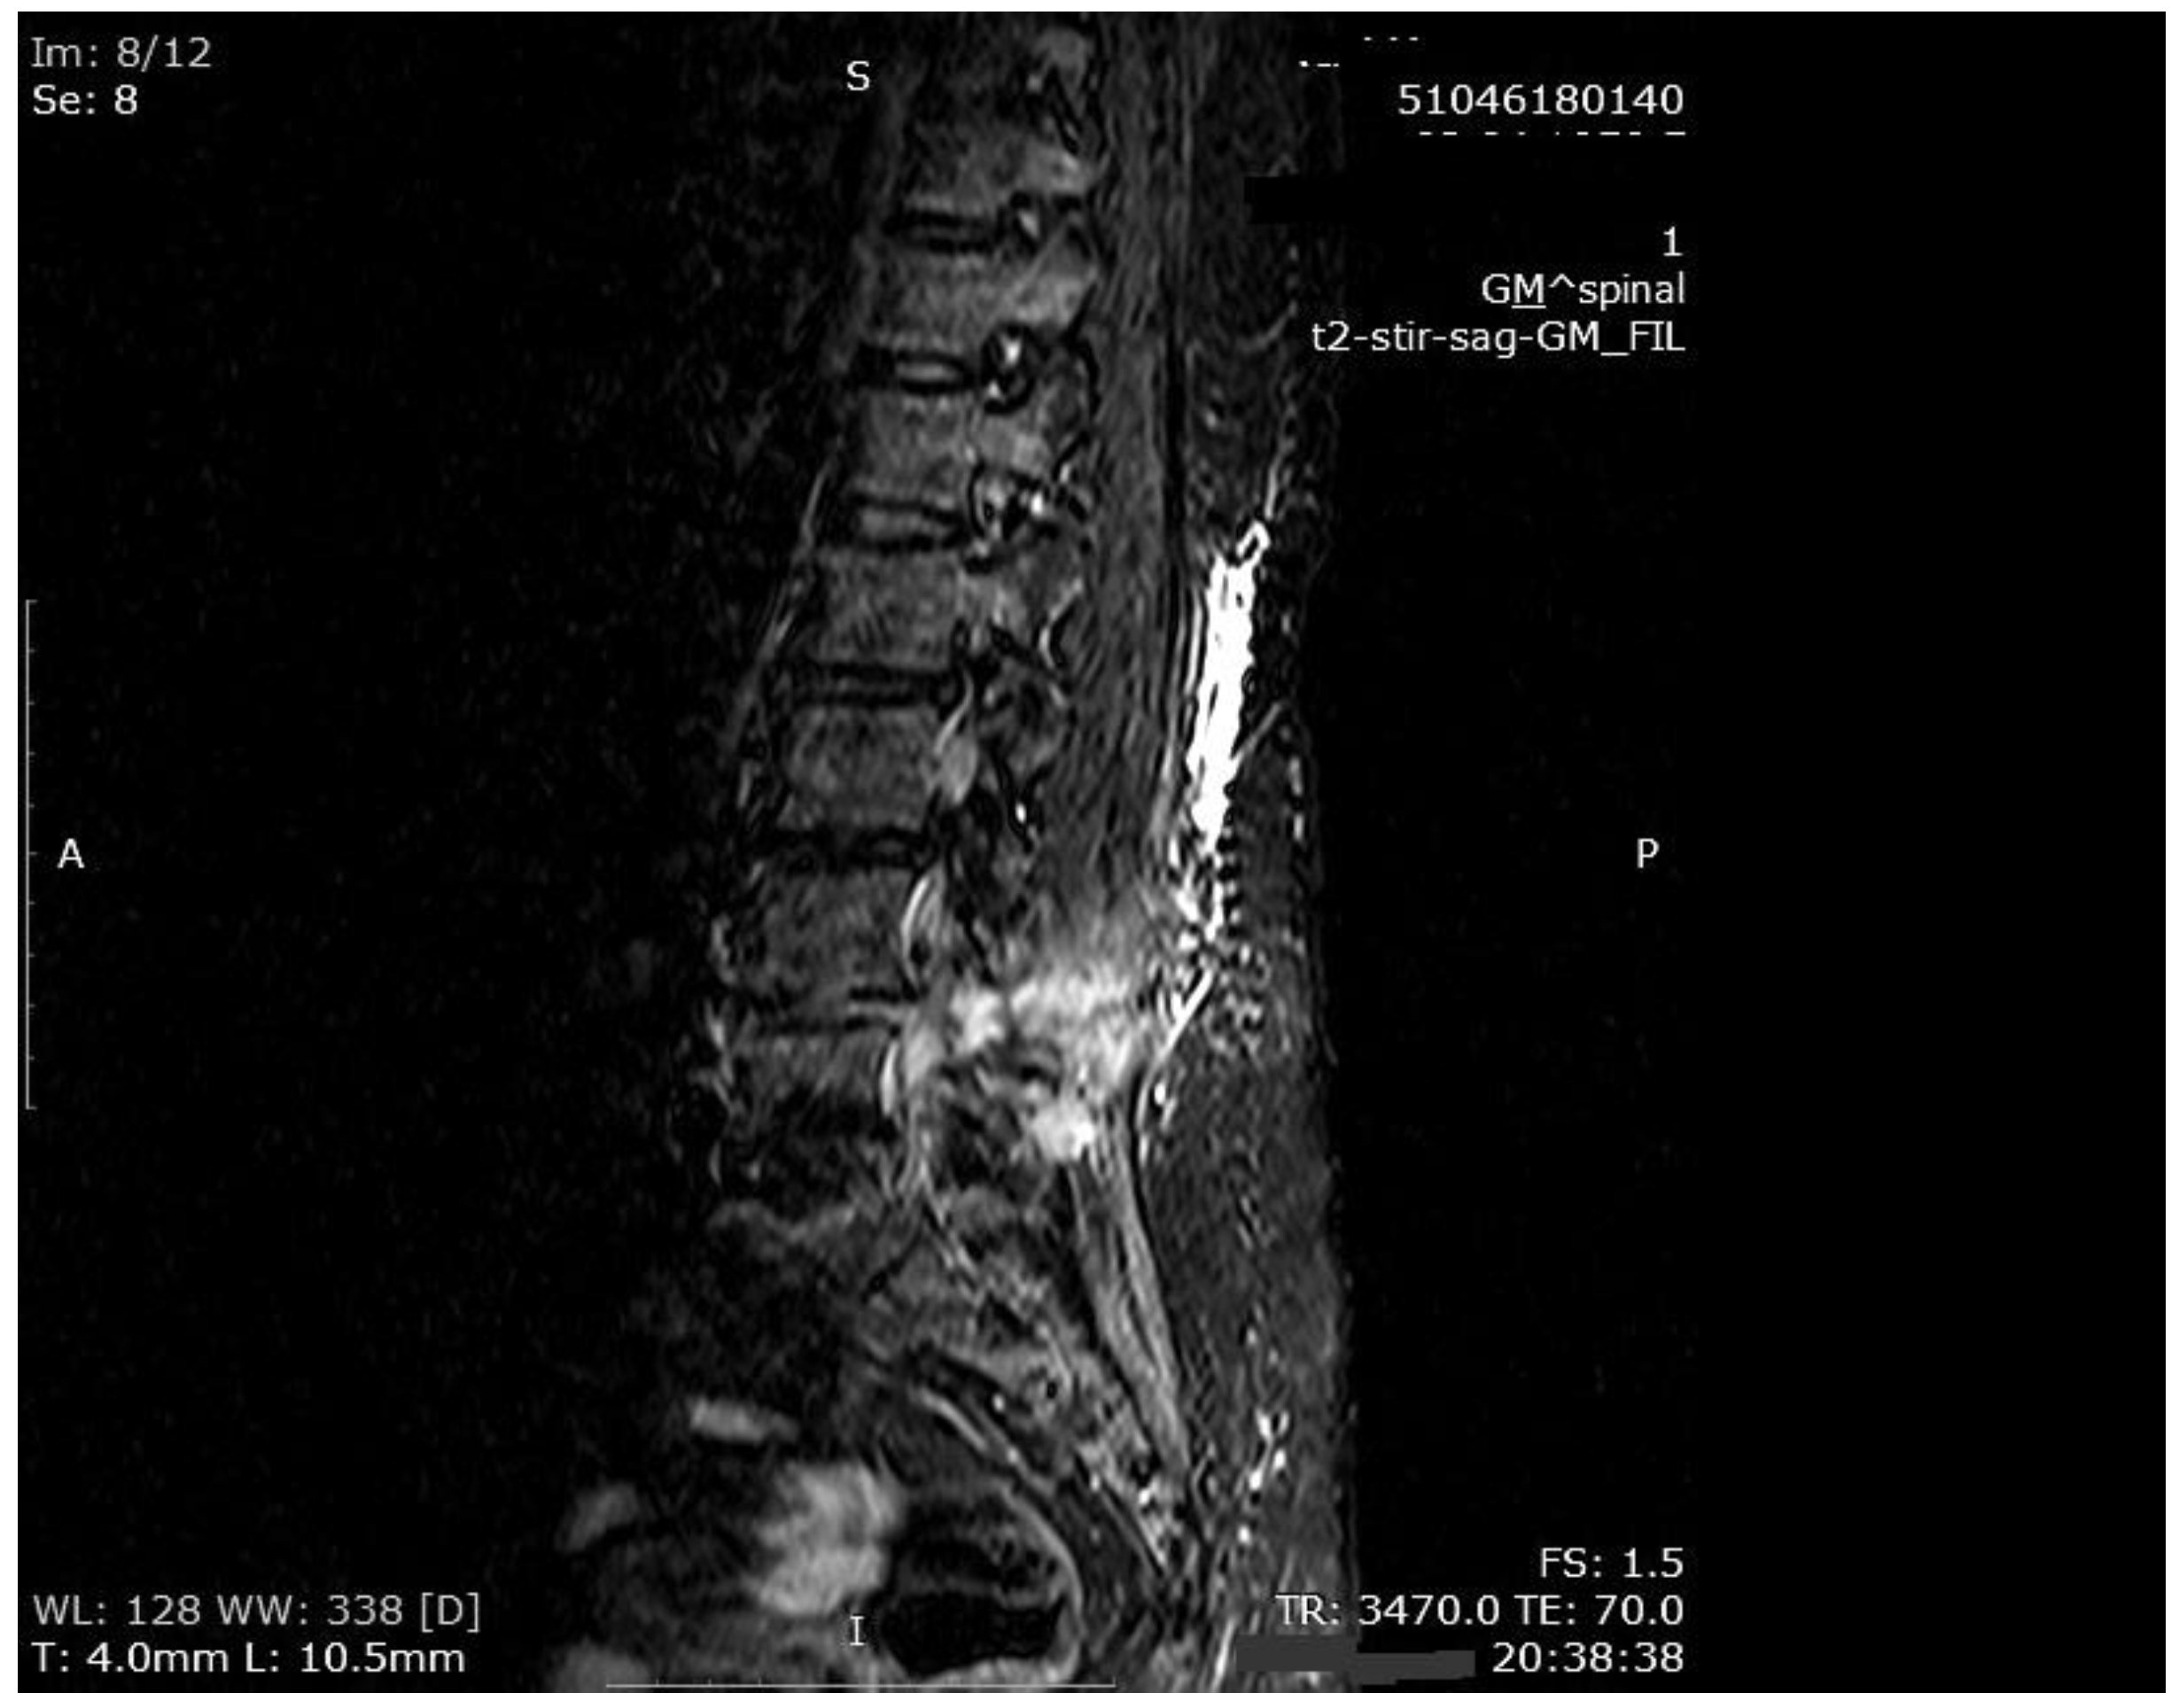

The mean number of total HBO2 sessions was 33 (±18.5) sessions. The HBO2 treatment was tolerated well by all patients except two. One patient had to receive analgesics (non-steroidal anti-inflammatories) before HBO2 sessions because she had severe back pain, and in one patient the treatment was interrupted for five days because of minor middle ear barotrauma. Improvements in clinical evaluations and laboratory findings were observed in all cases at the end of the HBO2 therapy. The mean erythrocyte sedimentation rate (ESR) value reduced from 76.1 (range, 6–129) to 45.7 (range, 5–81) mm/h, and the mean C-reactive protein (CRP) concentration reduced from 82.9 (range, 14–202) to 17.5 (range, 1–49.5) mg/L (normal limits; ESR: <20 mm/h, CRP: 0–5 mg/L). Infection resolution was adequately achieved in 12 of 13 patients on MR imaging at the end of HBO2 treatment or during the first month of follow-up (Figure 3, Figure 4 and Figure 5). There was no significant improvement in one patient. To extend the total clinical follow-up period up to three years (mean: 11 months; range, 1 month–3 years), telephone interviews were conducted to determine any recurrence of symptomatic clinical infection. No recurrence of infection, spinal instability, or deformity was seen in any patients.

Figure 3. MR imaging T1-weighted scan showing inflammatory infiltrates in the course of pre-HBO2 treatment.

Figure 4. MR imaging T2-weighted scan showing inflammatory infiltrates in the course of pre-HBO2 treatment.

Figure 5. MR imaging scan showing inflammatory infiltrates at the end of HBO2 treatment.